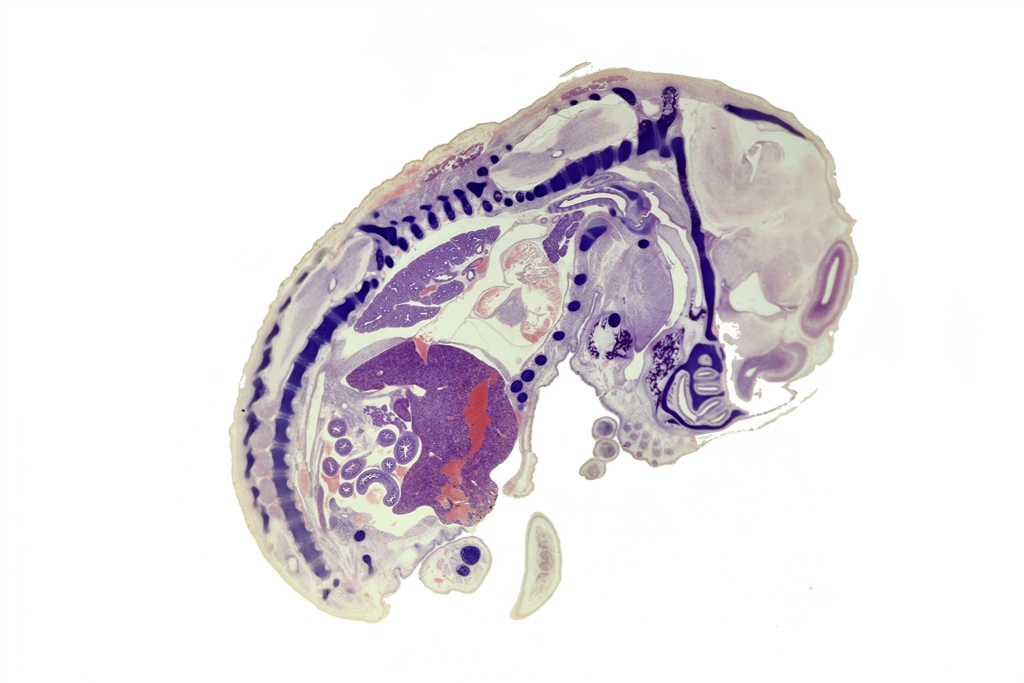

あえて無題のこの写真(何だろう?)